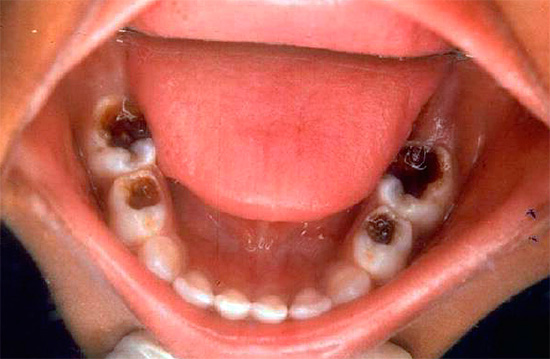

Una fotografia di un dente con una cavità profonda e cariata, che in qualsiasi momento può causare pulpite: